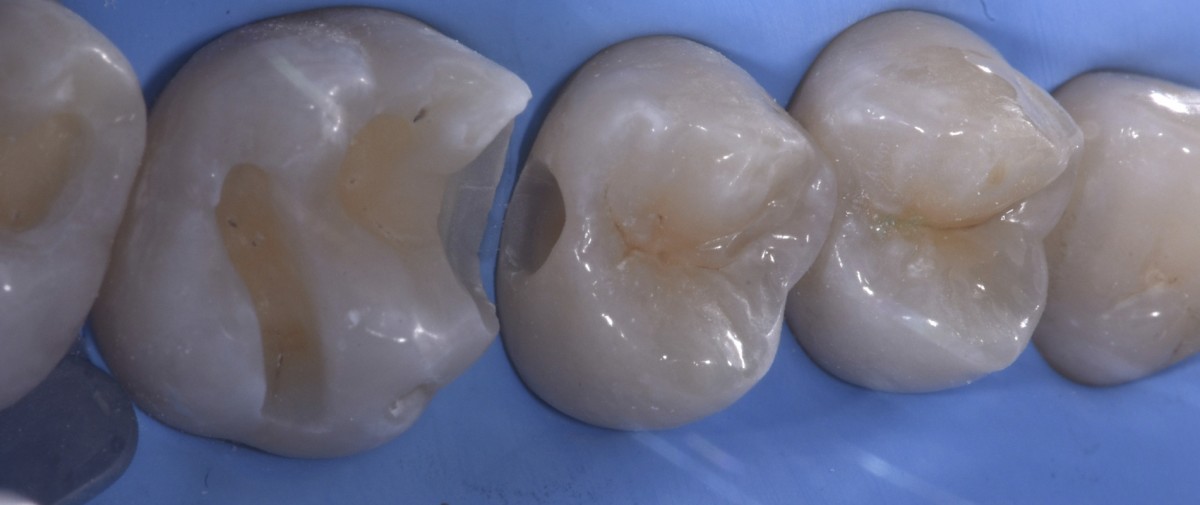

Detail of the prepared slot (Fig.4).